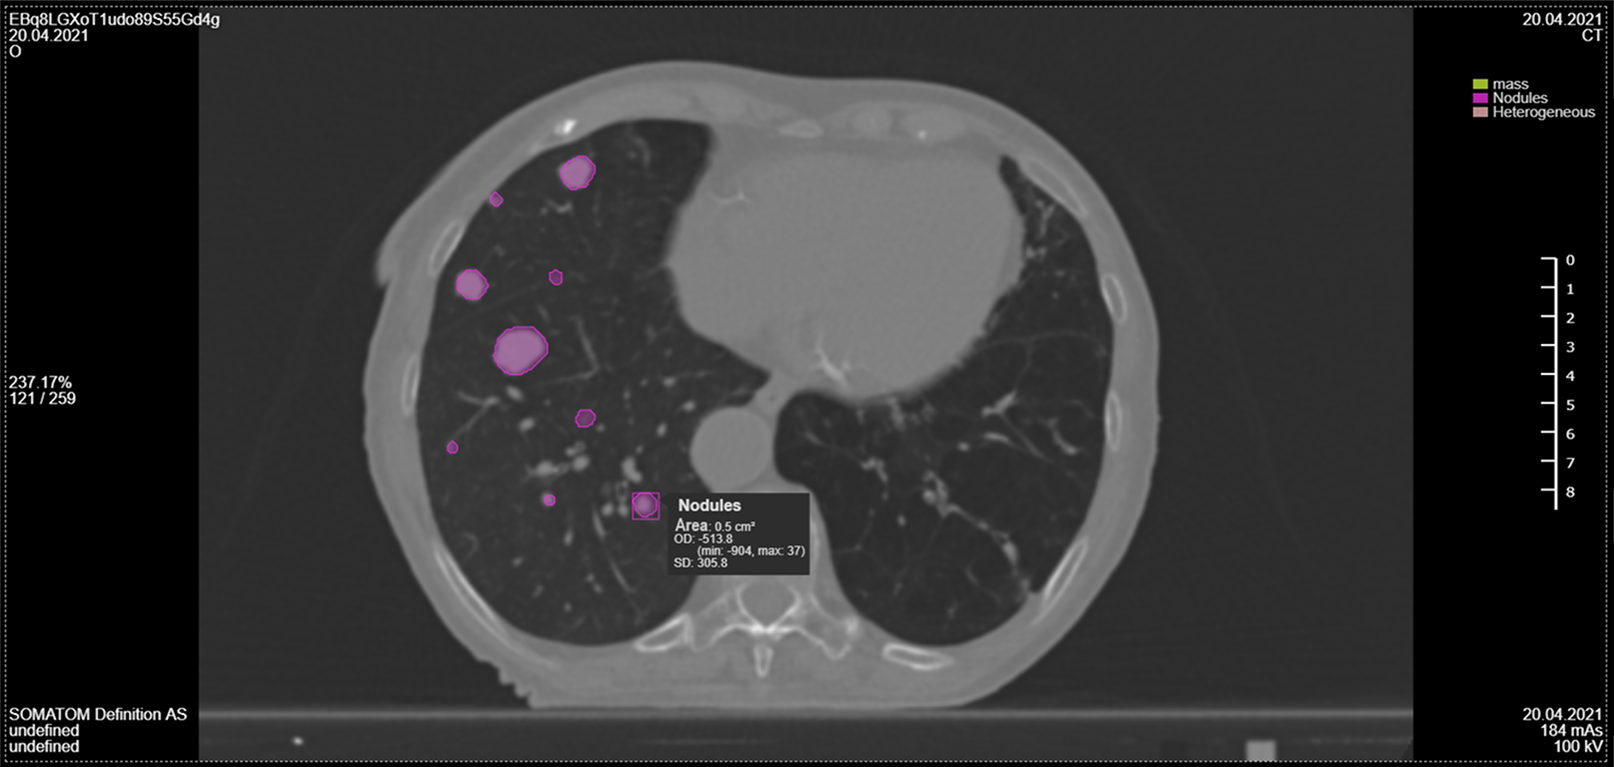

• Classifies nodules, masses, and pneumonia indicators for precise analysis

• Localizes pathologies with visual annotations on CT images